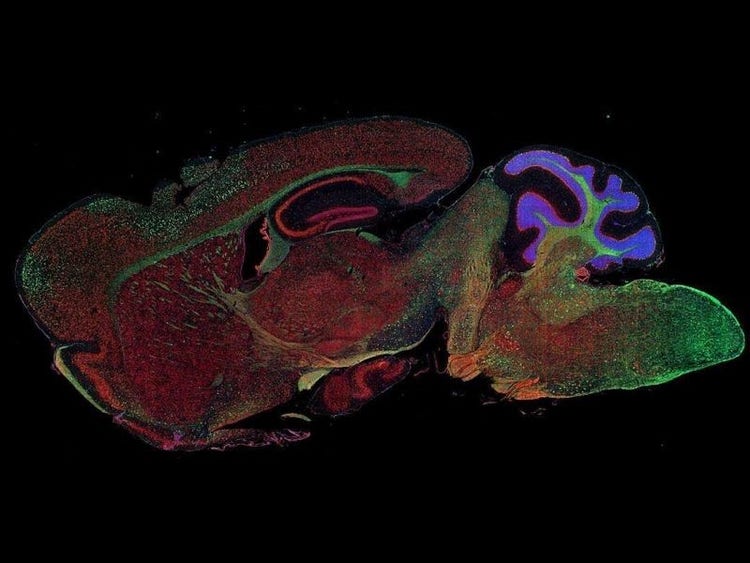

Fluorescence imaging of a mouse brain

尽管每幅图像近看各不相同,但将其拼接在一起则可组成一幅小鼠大脑的荧光图像。

英国科学家乔治·斯托克斯在用紫外线照射矿物萤石时首次观察到了矿物萤石发出的荧光,并创造了“荧光(fluorescence)”这个词。斯托克斯注意到荧光的波长比激发光的波长更长,这种现象现在被称为斯托克斯位移。无论是自然具有荧光的材料(称为原发荧光或自发荧光),亦或是经过有机染料处理后产生荧光的材料(称为次生荧光),荧光显微镜都是研究这些荧光发光材料的最佳工具。